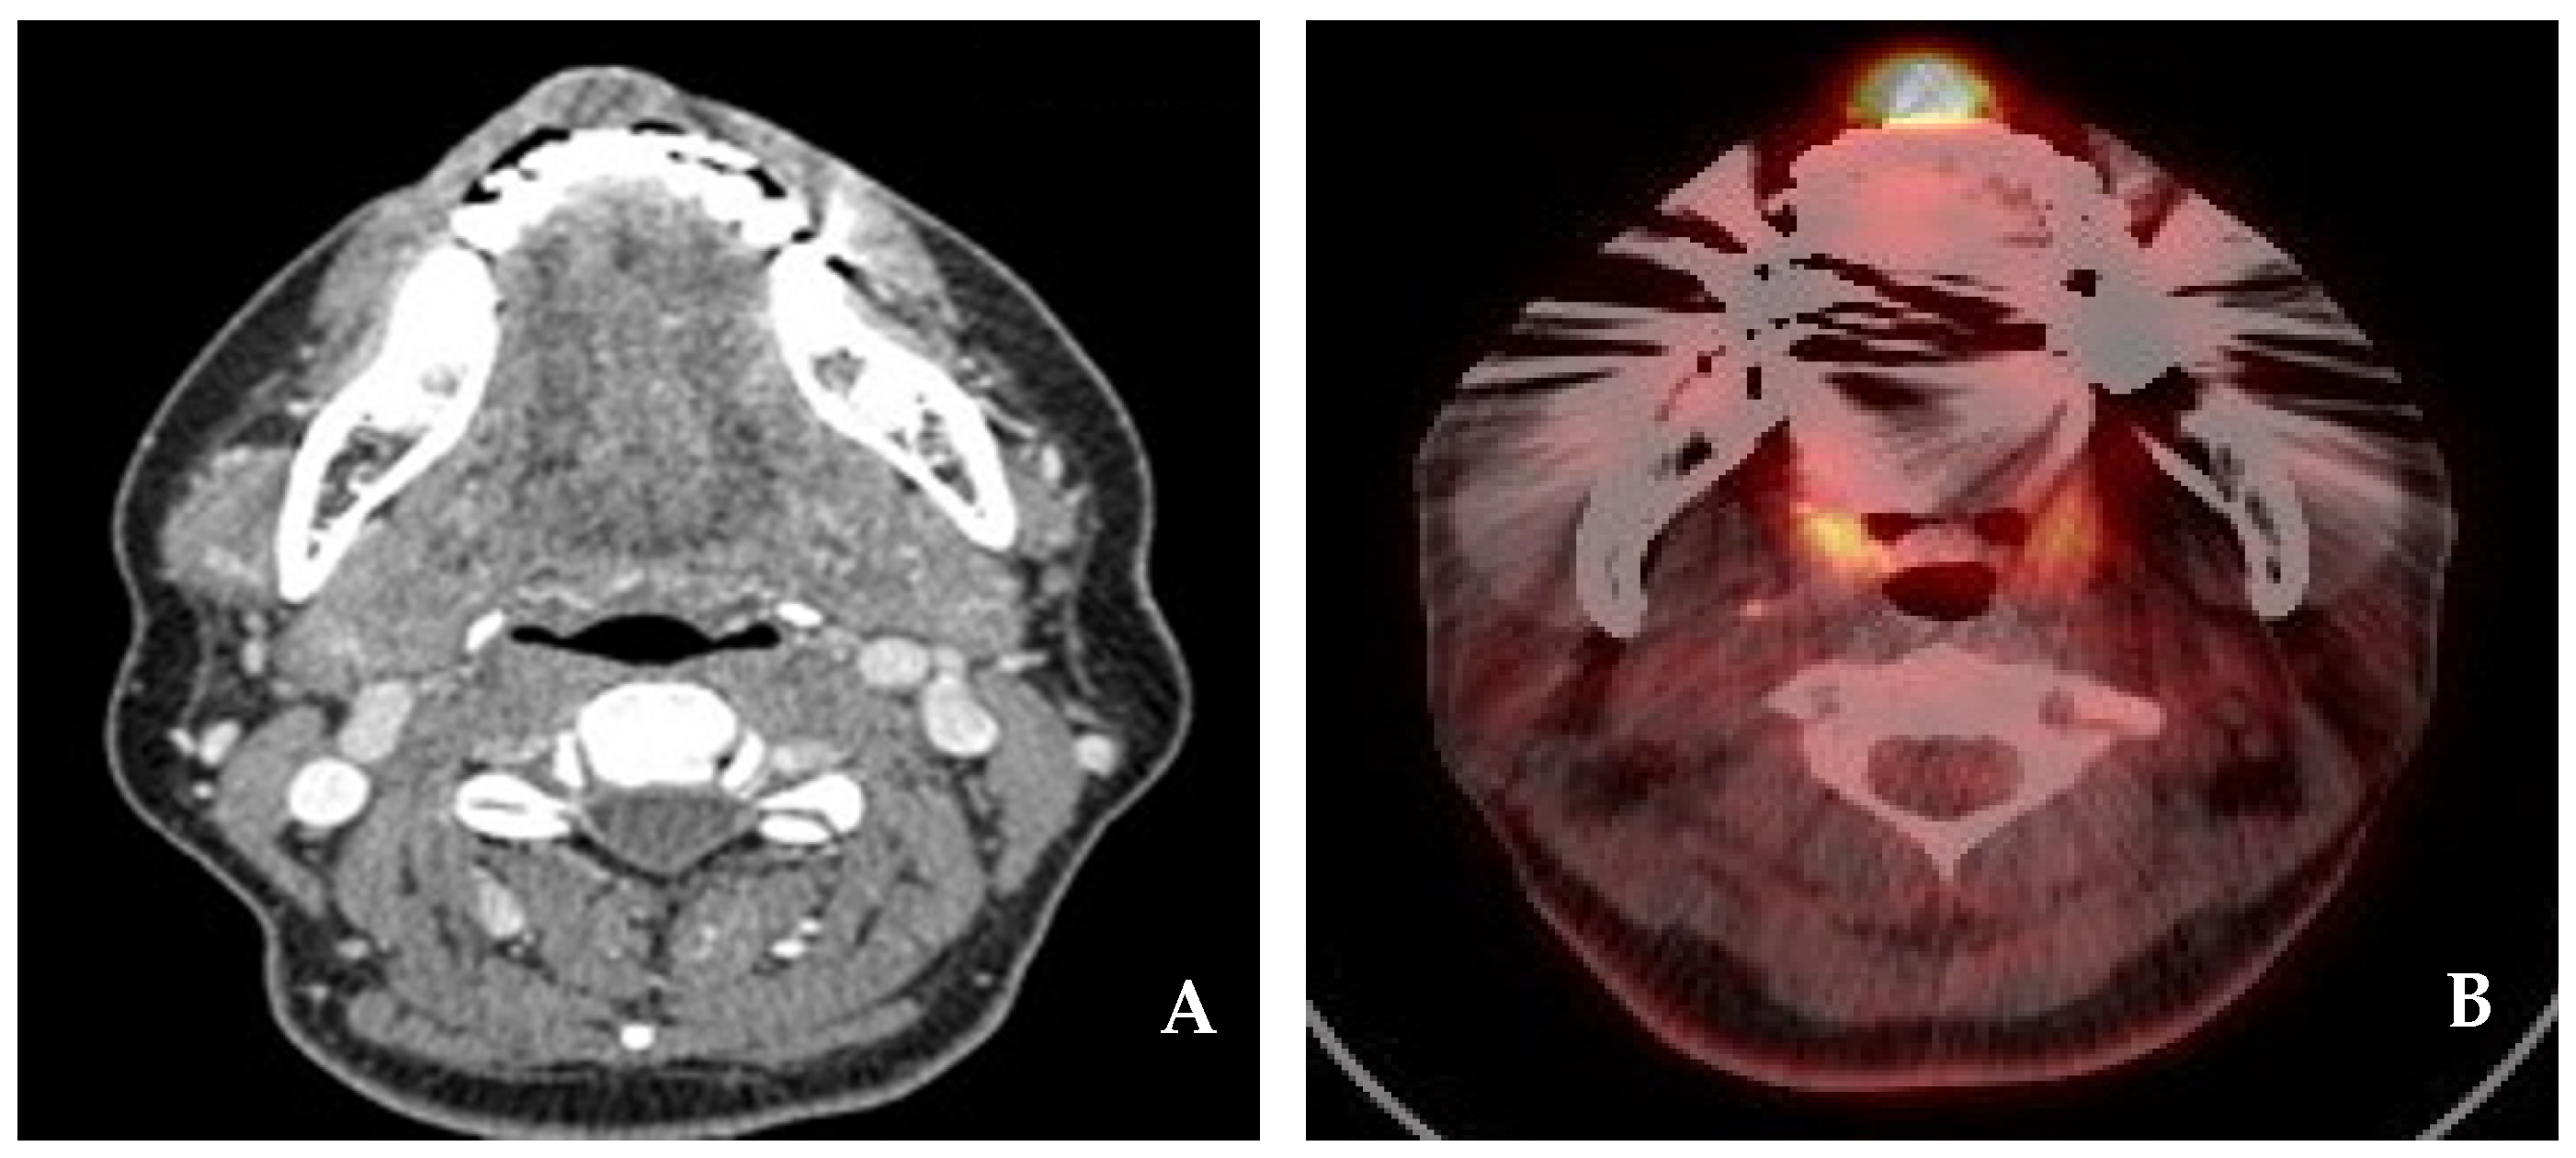

2.1. Case 1